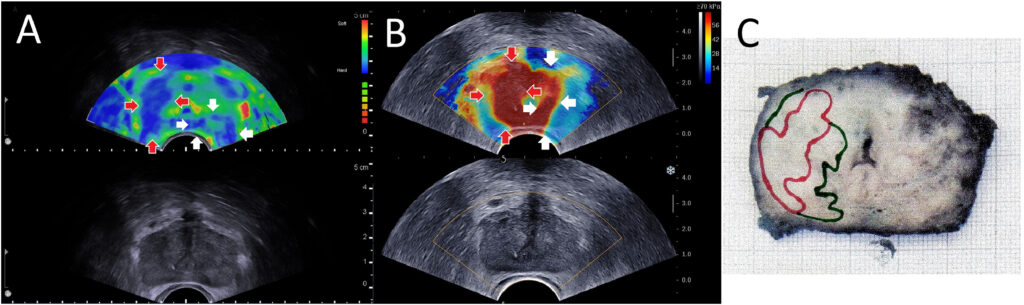

- Strain Elastography (SE): This technique involves applying slight pressure (compression) with the transrectal probe and measuring the resulting tissue deformation (strain). Harder tissue deforms less under compression than softer tissue. The ultrasound system computes relative strain and displays an elastogram – typically a color map overlaid on the B-mode image where, for example, blue might indicate stiff areas and red soft areas (or vice versa). It’s a qualitative or semi-quantitative method; often the stiffness of a region is compared to adjacent “normal” reference tissue or to the overall gland. Strain elastography can identify a stiff lesion (e.g., a cancer) as a focal area of low strain (hard) within the softer surrounding prostate. It requires a steady hand and often multiple compressions to get a usable image. Early studies of strain elastography in prostate cancer showed that it can improve cancer detection when used alongside TRUS, with reported sensitivity around 70–82% and specificity 60–95%. A meta-analysis by Zhang et al. found pooled sensitivity ~72% and specificity ~76% for strain elastography in detecting prostate cancer, using prostatectomy specimens as reference. These numbers are an improvement over conventional B-mode alone. Elastography tended to have particularly high negative predictive value – one study reported an NPV ~95–99% when no stiff areas were seen on elastography (suggesting a low chance of missing significant cancer). However, strain elastography has limitations: it provides relative stiffness (so results can vary with how compression is applied), and the presence of large BPH nodules or calcifications can affect readings. It also doesn’t give an absolute stiffness value.

- Shear-Wave Elastography (SWE): This is a more quantitative method. In SWE, the ultrasound probe emits a focused acoustic radiation force impulse (ARFI) into the tissue, which generates shear waves that propagate through the prostate. The speed of these shear waves is measured – stiffer tissue allows faster shear wave propagation. The result is typically an absolute measurement of Young’s modulus (kPa) or shear wave velocity (m/s) for each small region, which can be color-coded on an image. SWE provides a quantitative stiffness map without needing manual compression. For instance, a prostate cancer might show a stiffness of 80 kPa versus normal prostate ~30 kPa. Several studies have demonstrated the performance of SWE. For example, Boehm et al.found that using a cutoff of 50 kPa for suspect areas yielded a sensitivity ~81% and specificity ~69% for significant cancer (with higher stiffness correlating with higher Gleason grade). Another study reported that with a cutoff of 35 kPa, they achieved negative predictive value of 96% – meaning if the prostate had no area stiffer than 35 kPa, significant cancer was very unlikely. A 2019 meta-analysis (Yang et al.) concluded that SWE could be a “feasible technique to ameliorate PCa detection” and potentially reduce unnecessary biopsies. Furthermore, elasticity correlates with tumor grade: higher Gleason cancers tend to be stiffer. In one series, Gleason 6, 7, and ≥8 tumors had mean stiffness of ~92, 102, and 132 kPa respectively, showing a clear stepwise increase. This opens the possibility that elastography not only detects cancer but might help assess its aggressiveness noninvasively.

Elastography can be particularly helpful for cancers in the anterior fibromuscular stroma or deep transition zone, which are hard to visualize on B-mode but can be detected as focal stiff areas. It also may help distinguish benign stiff entities (like calcified BPH nodules) from cancer: BPH nodules can be firm but often not as uniformly stiff as cancer and have different elastographic patterns. However, overlap exists, and absolute diagnosis by elastography alone is not currently possible – it’s a complement to imaging and biopsy, not a replacement.

One challenge in implementing elastography widely has been the lack of standardization. Different machines have different scales and techniques (some use strain ratio calculations, others provide kPa values). There is also a learning curve to interpreting elastograms. Despite this, numerous studies validate that elastography significantly improves prostate cancer detection when added to TRUS, and can guide targeted biopsies. A recent (2025) review by Liang et al.concluded that ultrasound elastography has “significant advantages in diagnostic accuracy” for prostate diseases compared to conventional methods, though it noted the need for standardized protocols and broader availability of equipment. Elastography is also being investigated for treatment monitoring – for example, after focal therapy or radiation, elastography might detect residual stiff tumor versus softened treated tissue.

In summary, ultrasound elastography provides a virtual “finger” to palpate the prostate from the inside, mapping stiffness to highlight suspicious areas. It has shown improved detection of clinically significant cancers in many studies and is an exciting addition to the sonographer’s and urologist’s toolkit. As the technology matures and becomes more standardized, elastography could be routinely integrated into prostate ultrasound exams to decide where to biopsy or whether a patient can safely avoid biopsy (if the gland is entirely soft and unremarkable on elastography, for instance).